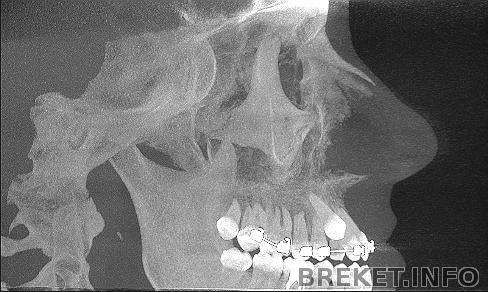

Вид сбоку

Вывод один - скорее бы операция